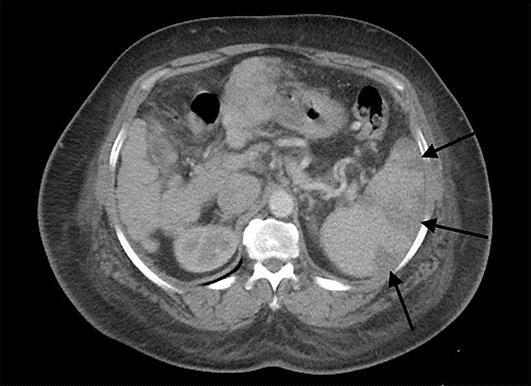

Spontaneous splenic infarction has been rarely reported as a complication of cirrhosis and portal hypertension. We describe the case of a 67-year-old female with past medical history of primary biliary cirrhosis presenting for a 1-day history of left upper quadrant pain. Investigations were in favor of splenic infarcts secondary to portal hypertension. The patient improved with conservative management and no recurrence was noted on further follow-up. Splenic infarction must be kept in mind when a patient with cirrhosis presents with left upper quadrant abdominal pain without a clear source.

自发性脾梗死作为肝硬化和门静脉高压的一种并发症鲜有报道。我们描述了一例67岁女性患者,其有原发性胆汁性肝硬化病史,因左上腹疼痛1天前来就诊。检查结果支持门静脉高压继发脾梗死。患者经保守治疗后病情好转,进一步随访未发现复发。当肝硬化患者出现左上腹腹痛且病因不明时,必须考虑到脾梗死的可能。